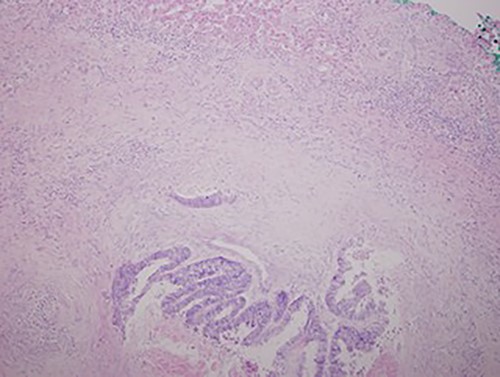

A chest X-ray at the time of admission showed right upper lobe mass (Fig. 1). Tru-Cut biopsy was performed and confirmed the diagnosis of non-small cell carcinoma (Figs 2 and 3). Multiple sections showed two nodules composed of well differentiated adenocarcinoma. The largest one measuring 4 mm from the resection margin, 2.5-cm away from hilar region and 5 mm from the outer surface. Smallest nodule was also composed of well-differentiated adenocarcinoma present 3 mm from the outer surface.

Hematoxylin and eosin stained histopathologic images illustrating lung tissue infiltrated by metastatic adenocarcinoma from colon (hematoxylin–eosin, original magnification ×200).